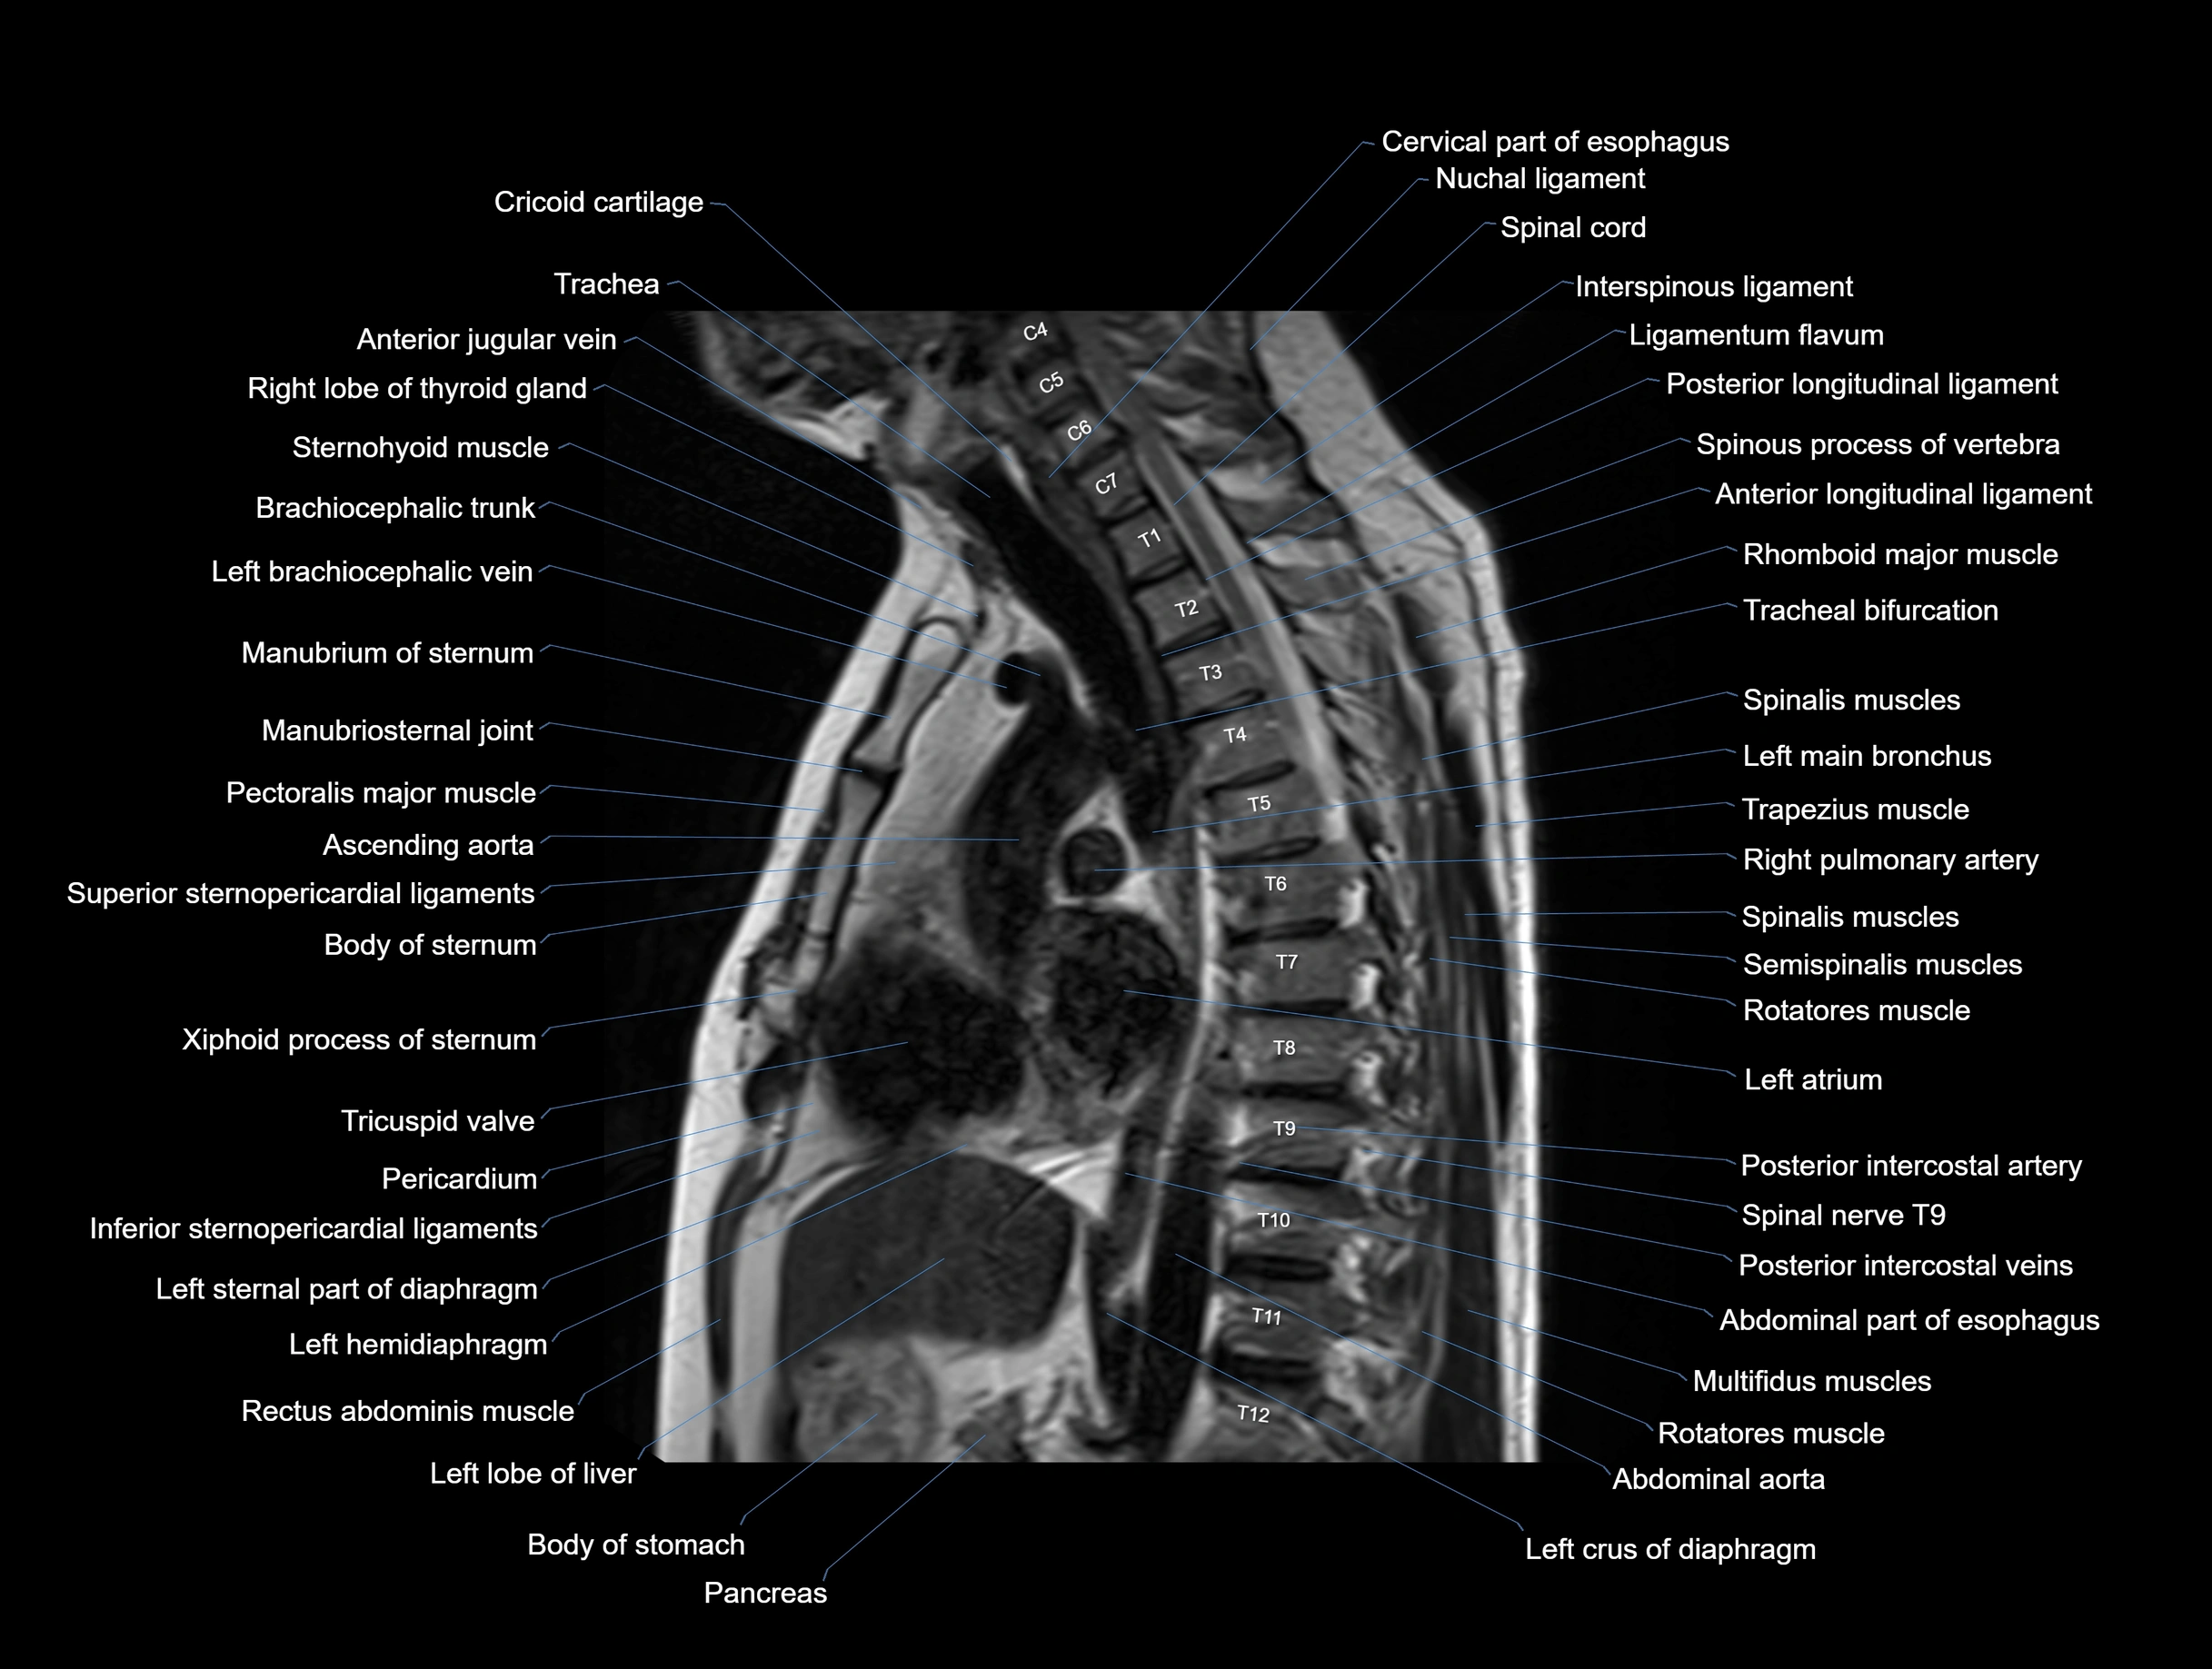

MRI images